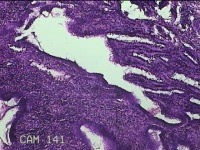

宫颈6点外缘、9点组织

性别

女

年龄

18岁

临床诊断

宫颈炎性疾病

一般病史

宫颈高危HPV感染

标本名称

大体所见

1.“宫颈6点外缘组织”:灰白粉红色不规则组织0.7x0.5x0.3cm两块。 2.“宫颈9点组织”:灰白粉红色不规则组织0.5x0.3x0.2cm一块。

良性病变。